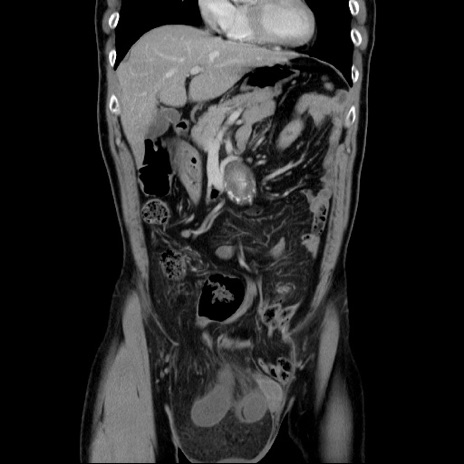

横断像

【症例】60歳代 男性

【主訴】右鼠径部膨隆

【現病歴】1年程前より右鼠径部膨隆あり。自己にて還納可能だったため放置していた。3時間前より右鼠径部の脱出を認め、還納困難となり受診。

【身体所見】右鼠径部に小児頭大の膨隆あり。弾性硬であり、用手還納は困難。左鼠径部にも膨隆を認める。脱出はなし。